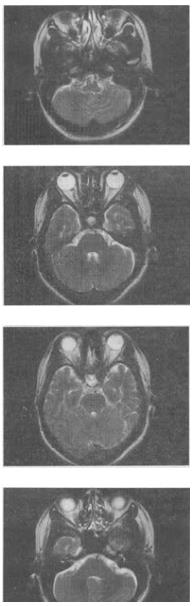

女,41岁,阵发性头痛伴恶心,呕吐20余天,MRI影像如图,最可能的诊断是()。

A:双侧筛窦息肉

B:双侧筛窦炎

C:双侧筛窦未见明显异常

D:双侧筛窦真菌感染

E:双侧筛窦过敏性炎症